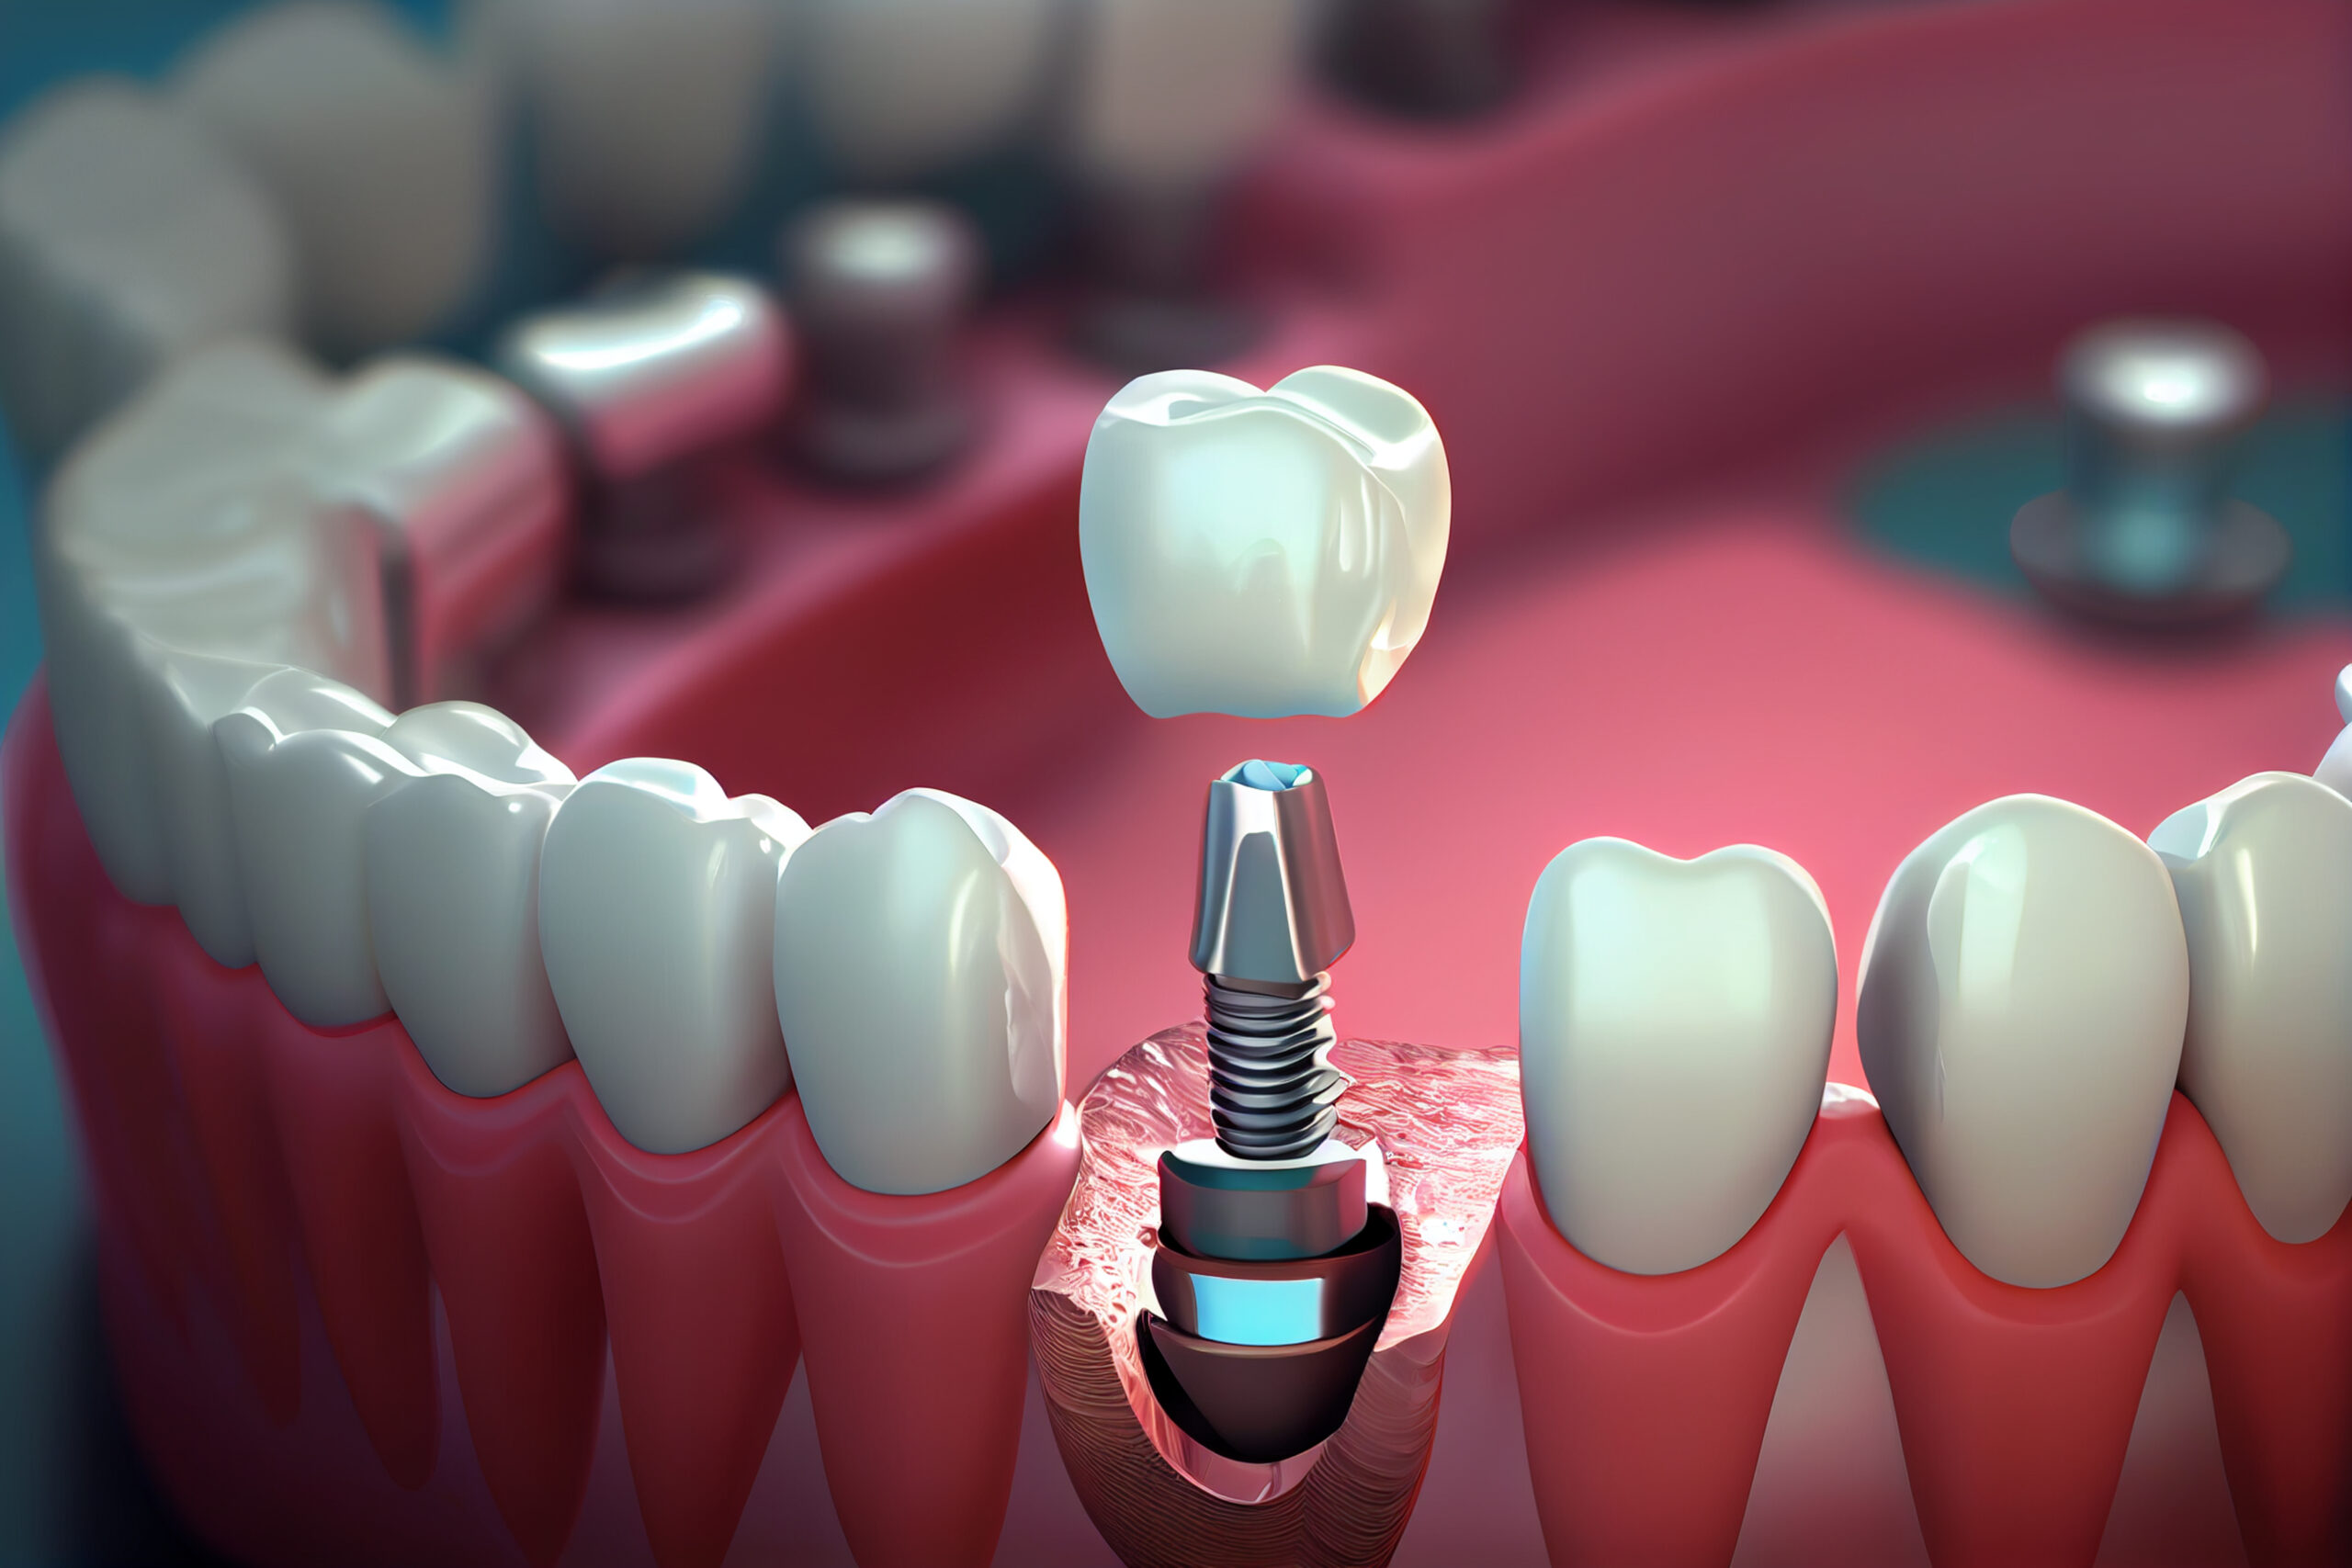

Implanty zębowe (implanty dentystyczne) to innymi słowy zamienniki korzenia zębowego, które umiejscawiane są w kości żuchwy bądź szczęki. Ich osadzenie pozwala stworzyć koronę, most lub protezę, która pozwoli uzupełnić braki w uzębieniu. Implanty zębowe to opcja, dzięki której nie maskujemy niedoskonałości, a uzupełniamy uśmiech w prawidłowo funkcjonujący oraz prezentujący się naturalnie nowy ząb. Wykonanie z biozgodnego tytanu sprawia, że organizm doskonale go przyjmuje, a prawidłowo chirurgicznie wszczepiony implant zostaje obudowany przez kość (tzw. osteointegracja), dzięki czemu ząb jest stabilny i mocno osadzony.

Sam implant na tym etapie nie uzupełnia braku w uzębieniu. Pełna funkcjonalność zapewniona jest dopiero po zamocowaniu w implancie korony, mostu lub protezy. W części protetycznej uzupełniania uśmiechu – wykonywanej po pełnym procesie osteointegracji – możliwe jest założenie nowego zęba lub zębów.